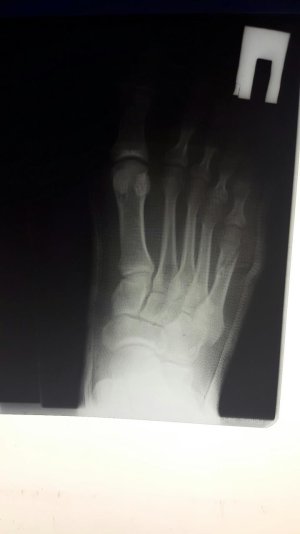

Здравствуйте. Мне 38 лет. Перелом 5-ой плюсневой.

Приложенные снимки - на следующий день после случившегося. Сразу в гипс на 5 недель. Ни в травмпункте, ни в поликлинике лечащий врач даже на упоминали операцию.

Только в травмпункте доктор сказал "... с незначительным смещением, поэтому просто гипс на месяц."

Посмотреть вложение 13116 Посмотреть вложение 13117